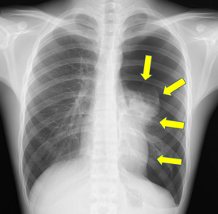

用线照片的肺的枯萎,根据状态,如下给气胸的程度分类。

轻微气胸:顶端面积(肺的第一名上的部分)也比锁骨的高度是在上边的状态。

中度气胸:肺尖部也比锁骨低的状态。轻微和高度的中间程度。

高度的气胸:肺完全枯萎或者离那个近的状态。